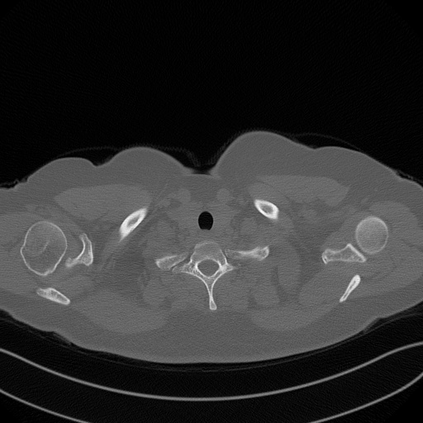

Low-Dose Computed Tomography (LDCT) technique, which reduces the radiation harm to human bodies, is now attracting increasing interest in the medical imaging field. As the image quality is degraded by low dose radiation, LDCT exams require specialized reconstruction methods or denoising algorithms. However, most of the recent effective methods overlook the inner-structure of the original projection data (sinogram) which limits their denoising ability. The inner-structure of the sinogram represents special characteristics of the data in the sinogram domain. By maintaining this structure while denoising, the noise can be obviously restrained. Therefore, we propose an LDCT denoising network namely Sinogram Inner-Structure Transformer (SIST) to reduce the noise by utilizing the inner-structure in the sinogram domain. Specifically, we study the CT imaging mechanism and statistical characteristics of sinogram to design the sinogram inner-structure loss including the global and local inner-structure for restoring high-quality CT images. Besides, we propose a sinogram transformer module to better extract sinogram features. The transformer architecture using a self-attention mechanism can exploit interrelations between projections of different view angles, which achieves an outstanding performance in sinogram denoising. Furthermore, in order to improve the performance in the image domain, we propose the image reconstruction module to complementarily denoise both in the sinogram and image domain.